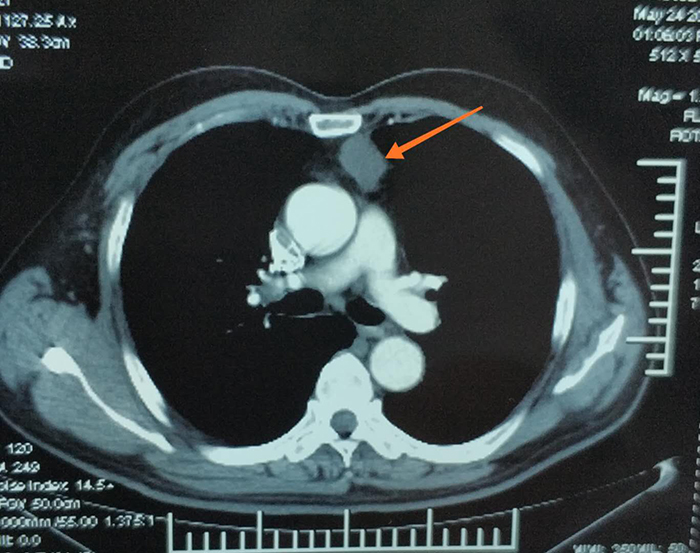

术前胸CT

然而,天有不测风云!一周前王大爷有些慌了,因为他在体检时发现胸腔前纵膈占位!焦虑的王大爷,四处打听,慕名找到了丹东市第一医院胸外科王勇智医生。王勇智医生一边安慰焦躁的王大爷,一边认真地观看胸部CT,并建议手术治疗。王大爷当即表示立即住院,并恳请王勇智医生担任自己的主刀医生。王勇智医生和他的团队对王大爷的身体做了全面的评估,根据王大爷的具体情况决,定采用微创的胸腔镜手术,并按照快速康复外科(Enhanced Revovery After Sergery,ERAS)的理念,对王大爷进行治疗和康复。